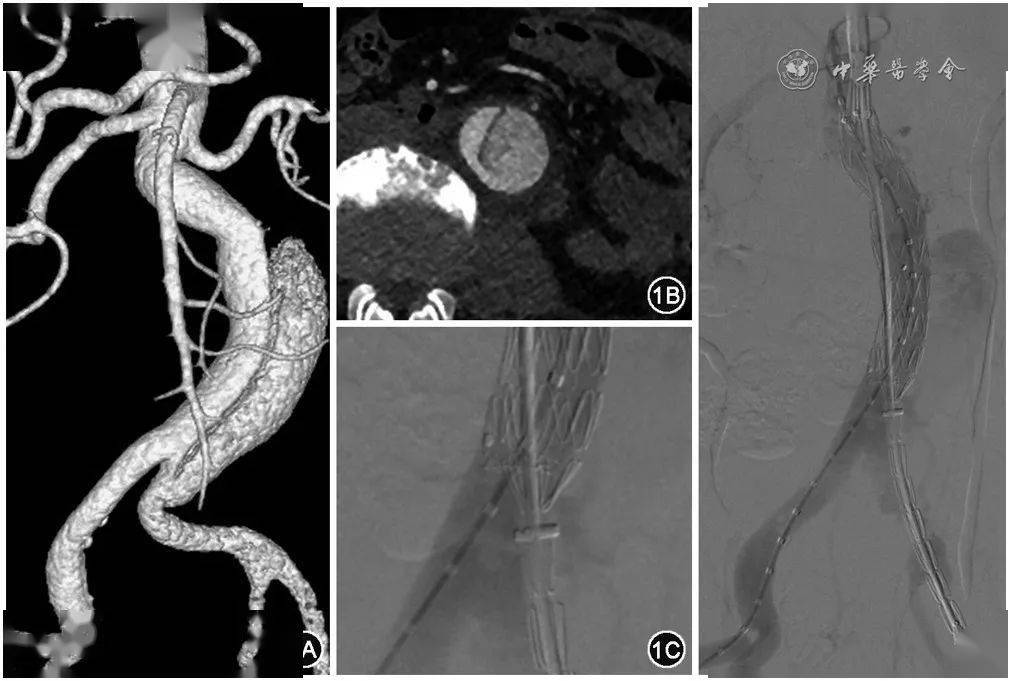

王暾孤立性腹主动脉夹层的腔内修复治疗

该患者因腰痛入院,ct发现腹主动脉夹层.